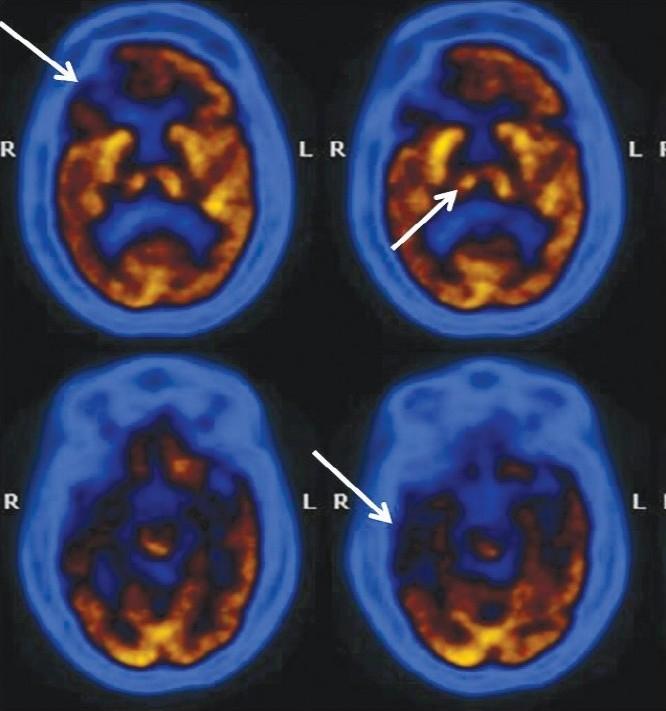

In the patient population included in our study group 36 were normal, 39 had MCI, 40 had AD, 14 had FTD, and 13 had DLBD and 11 dementia due to other miscellaneous causes. MCI patients showed primarily reduced tracer uptake in the mesio-temporal cortex. AD patients showed reduced tracer concentration in temporo-parietal lobes, while patients with advanced diseases showed frontal lobe disease additionally. In subjects of FTD, reduced radiotracer uptake in the fronto-temporal lobes was noted. In addition, FTD patients also showed basal ganglia defects. In contrast the DLBD patients showed globally reduced FDG uptake including severely affecting the occipital cortices.

在我们研究组纳入的患者群体中,36人正常,39人患有MCI,40人患有AD,14人患有FTD,13人患有DLBD,11人因其他各类病因患有痴呆。MCI患者主要表现为内侧颞叶皮质示踪剂摄取减少。AD患者颞顶叶示踪剂浓度降低,而晚期疾病患者还表现出额叶病变。在FTD受试者中,额颞叶放射性示踪剂摄取减少。此外,FTD患者还表现出基底神经节缺陷。相比之下,DLBD患者表现为FDG摄取整体减少,包括严重影响枕叶皮质。